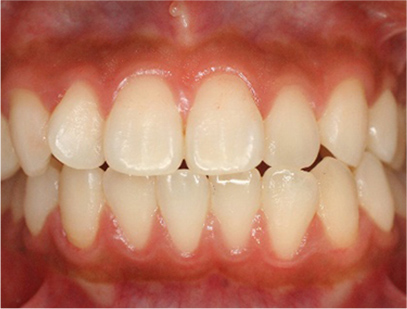

• 正面